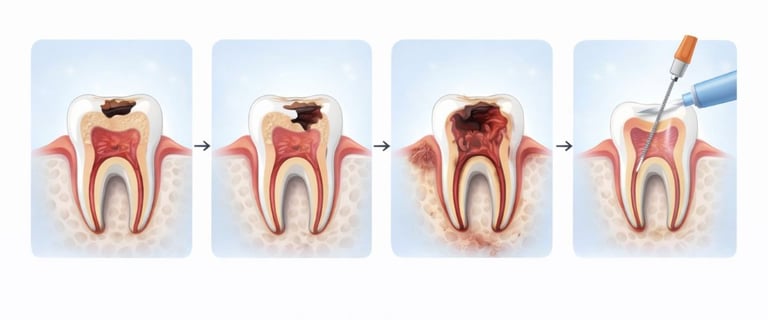

STEP-BY-STEP RCT PROCESS

Diagnosis & X-ray – To assess infection and tooth condition

Removal of infected pulp – Cleaning the root canals

Disinfection & shaping – Prevents reinfection

Filling & sealing – Strengthens the tooth internally

Crown placement (if required) – Restores chewing function